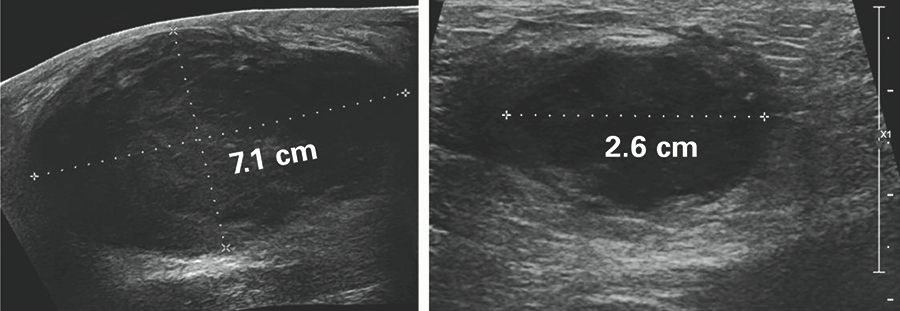

Tratamiento para el cáncer de mama sin cirugía